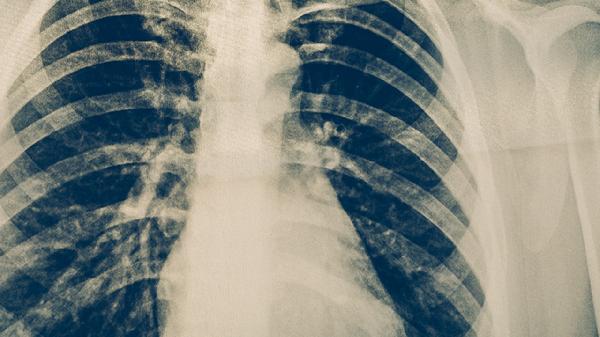

胸部X線能顯示肺結(jié)核的典型影像特征,如上肺野浸潤影、空洞形成、纖維條索影等。該檢查具有輻射量低、成像快速的優(yōu)點(diǎn),可作為初篩手段。但早期肺結(jié)核或免疫功能低下患者的X線表現(xiàn)可能不典型,需結(jié)合臨床癥狀和其他實(shí)驗(yàn)室檢查結(jié)果。

胸部CT檢查對(duì)肺結(jié)核的診斷具有更高敏感性,能清晰顯示微小病灶、淋巴結(jié)腫大及早期空洞。高分辨率CT可發(fā)現(xiàn)X線難以顯示的粟粒性肺結(jié)核,增強(qiáng)CT有助于鑒別結(jié)核球與惡性腫瘤。該檢查適用于X線結(jié)果不明確或需要評(píng)估病變范圍的患者。